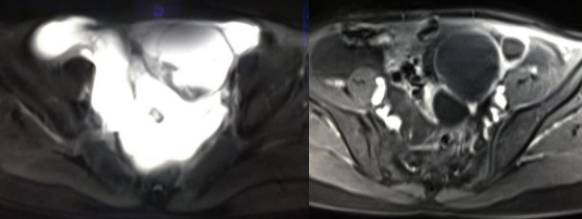

MR检查:

病理结果:黄体血肿

根据时间不同MR信号也有所不同,TIWI脂肪抑制序列可以鉴别脂肪和出血。

卵巢囊肿:呈均匀的T1WI 低信号,T2WI 高信号,边界清楚,壁薄,大多数病灶直径≤5 cm,但囊肿的起源及定性诊断困难。

巧克力囊肿:常呈多发的单囊或多囊改变,病灶大小不等,囊壁厚薄不均,囊内信号复杂,囊内或各囊腔间血液因出血时期不同,信号常呈多样性,囊肿内反复出血、破裂,形成相互粘连的多房性囊肿,是其较为特征性的表现。

在鉴别卵巢畸胎瘤、出血性囊肿或巧克力囊肿时,MR 脂肪抑制T1WI 可明确肿块内高信号成分是脂肪还是出血,同时因为脂肪组织与非脂肪组织的共振频率不同,在两者交界处沿磁场频率编码方向出现化学位移伪影,但出血性囊肿与巧克力囊肿的鉴别偶尔较为困难。